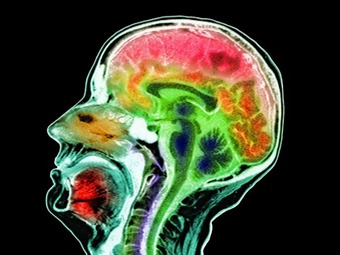

La mal de Alzheimer es la forma más común de demencia, afectando a cerca de 40 millones de personas alrededor del mundo. Esta enfermedad crónica neurodegenerativa se caracteriza por la pérdida progresiva del tejido cerebral, junto con una acumulación de dos proteínas: amiloide-β y tau.

Aunque ambas moléculas juegan un papel importante en la función de las células cerebrales, pueden degradarse y agruparse dentro y fuera de la célula, lo que altera los procesos celulares normales y, eventualmente, conduce a su muerte.

Los científicos descubrieron que las agrupaciones anormales de tau comienzan dentro de las neuronas del hipocampo, área cerebral crucial en el aprendizaje y la memoria, antes de expandirse hacia la corteza, la región responsable de las funciones cerebrales superiores como el pensamiento, la atención, la conciencia y el lenguaje.

El nuevo hallazgo resta importancia al papel de la proteína amiloide, la cual desde hace tiempo ha sido el foco de la investigación en torno al Alzheimer, y sugiere que en un futuro los esfuerzos deben centrarse en la lucha contra la proteína tau.